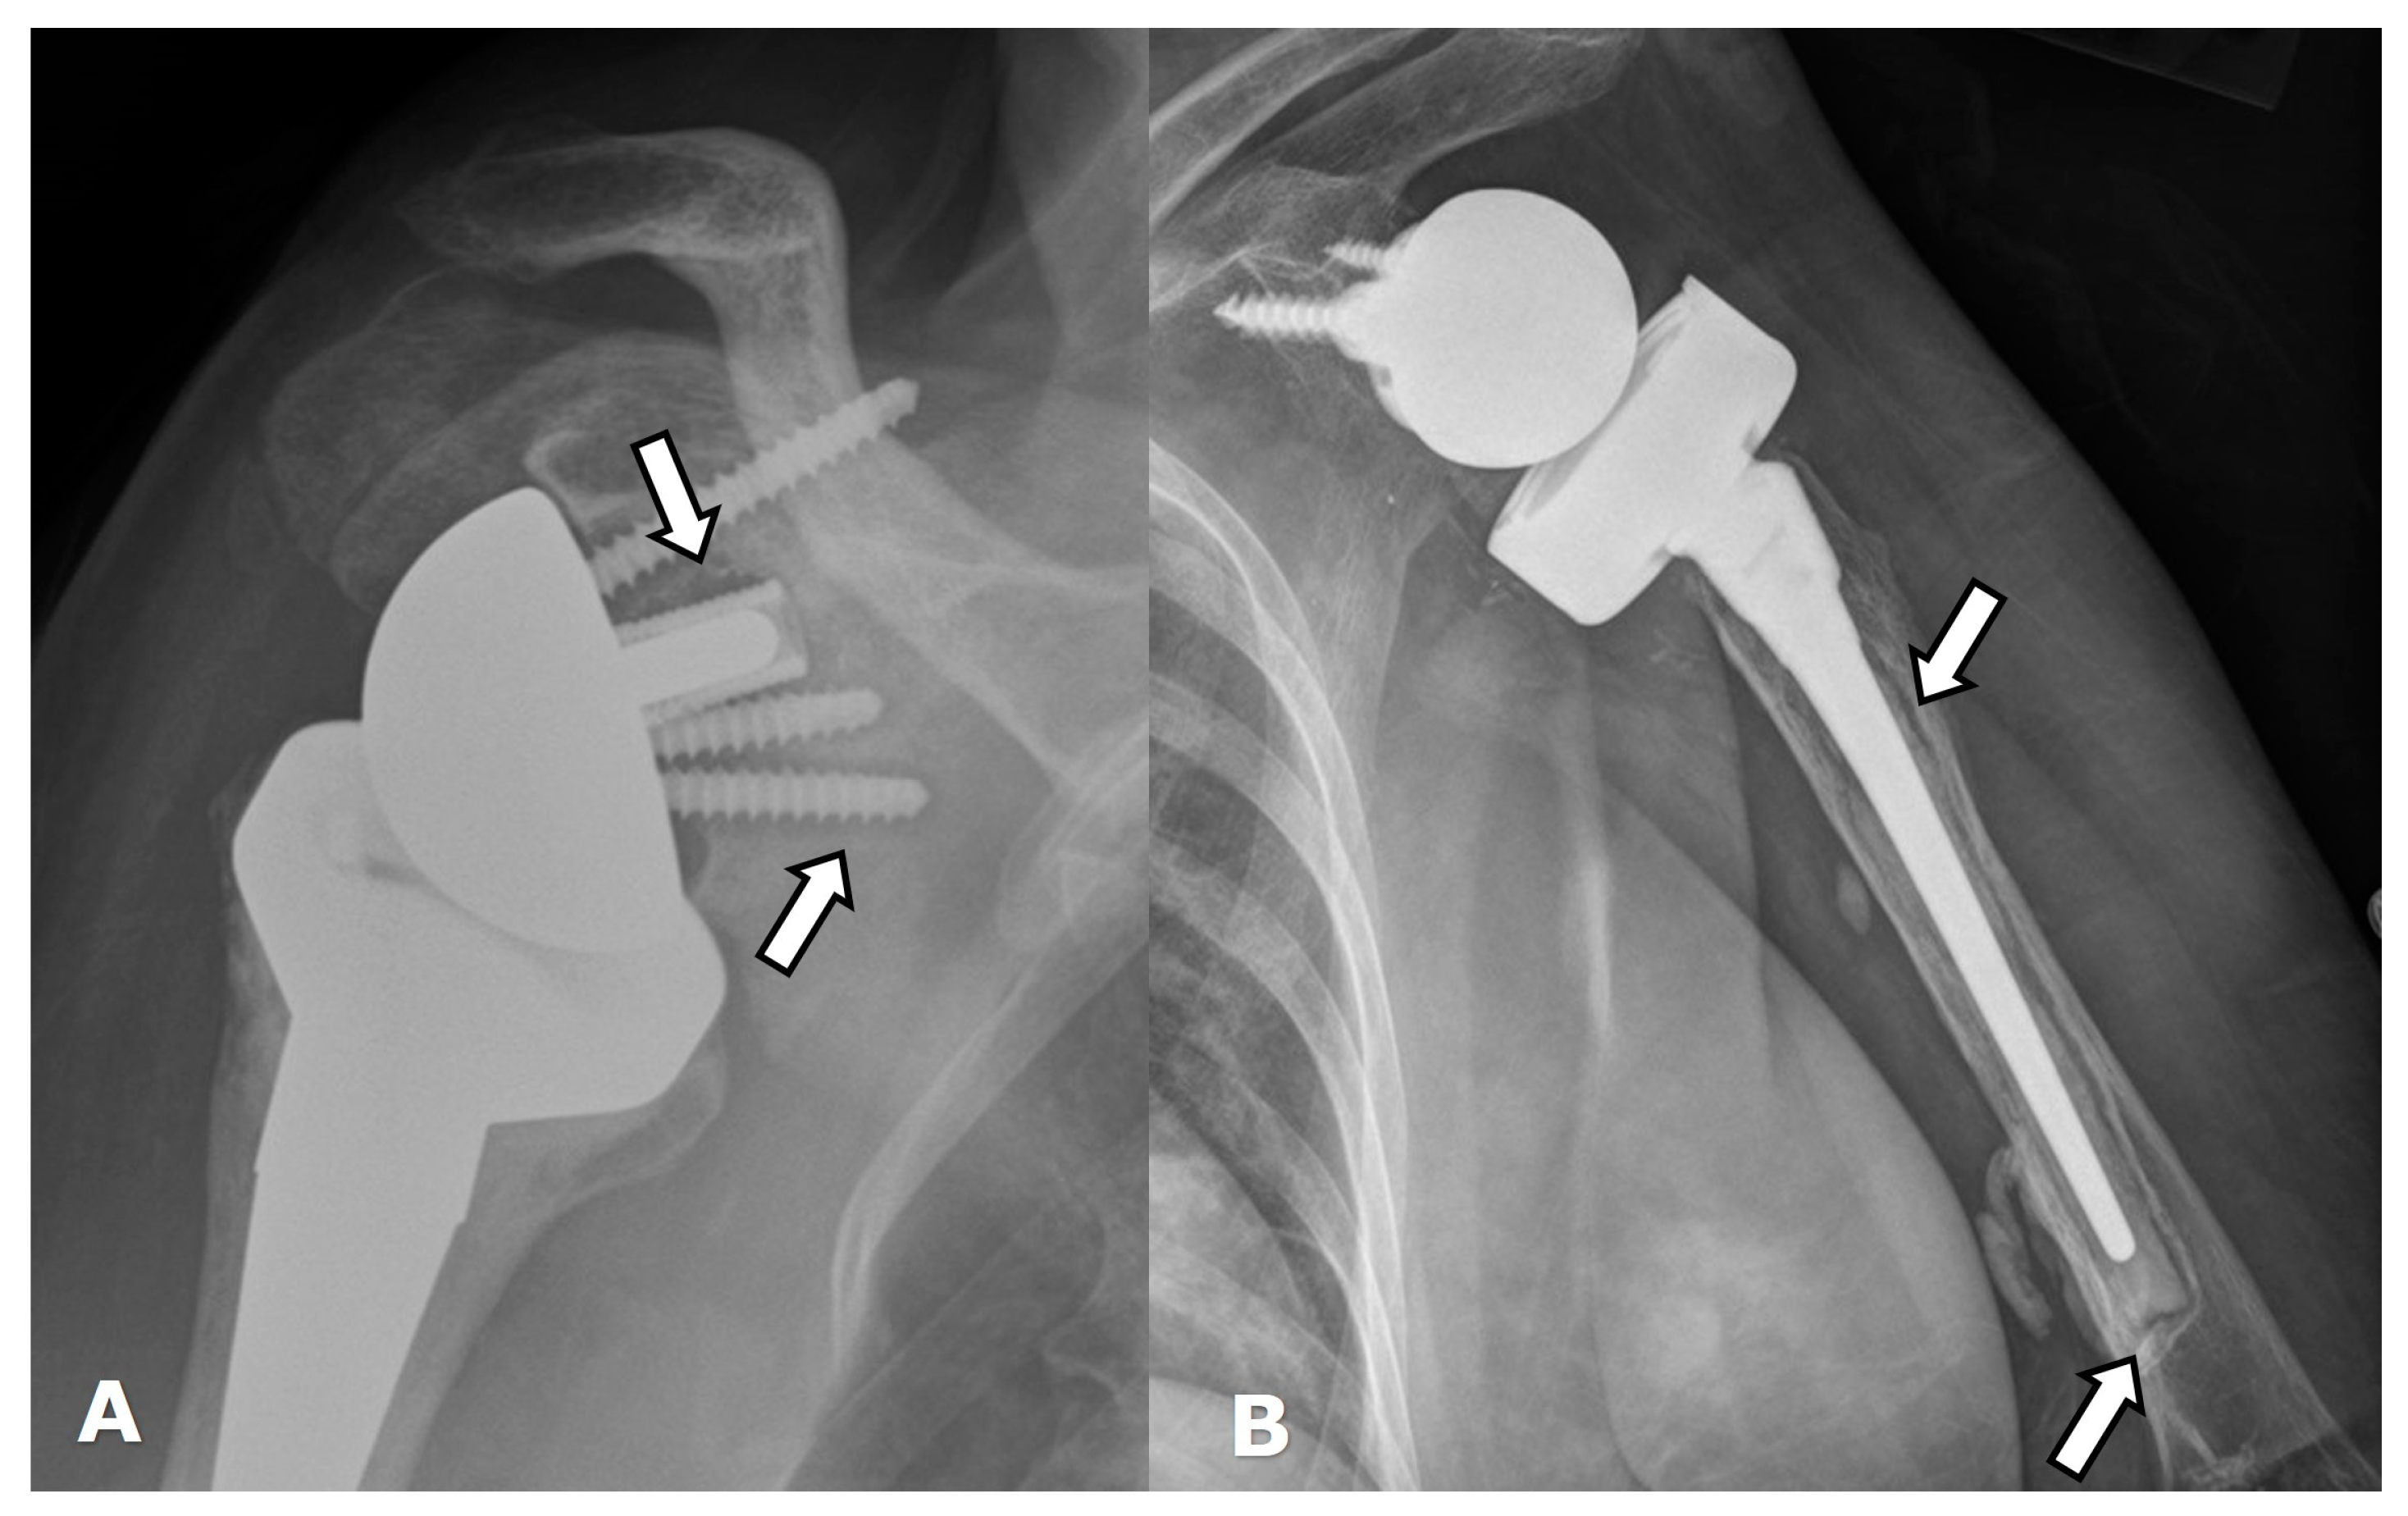

5.1.3. Anatomic Total Shoulder Arthroplasty (ATSA)

5.2. Reverse Arthroplasty

Reverse Total Shoulder Arthroplasty (RTSA)